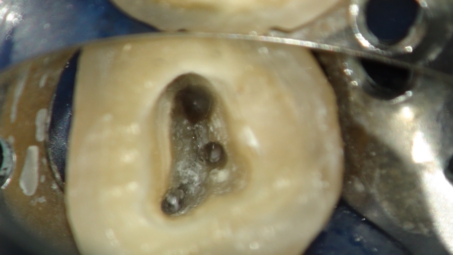

マイクロスコープ

根管治療にはマイクロスコープは必須です

さて、この3)を可能にするのがマイクロスコープによる根管治療です。

狭くて暗い根管の中を適切に清掃し、感染の除去を行う場合、20倍以上に拡大して観察が出来、診ている術者の視線の軸と光の軸が一致し、完全に見えるのがマイクロスコープです。

逆にマイクロスコープなくての根管治療は、暗闇の中で手探りで掃除をしているようなもので、上手くいく方が不思議に思えるような処置であると言っても過言では無いと思います。

当院ではマイクロスコープを用いた精密な根管治療を行っております。